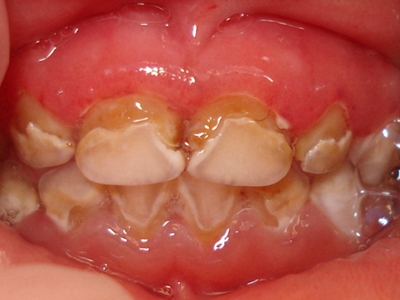

牙龈炎是发生于牙龈组织的炎症,患者可出现牙龈出血伴肿胀、发红、正常形态改变和偶尔不适等症状。本病主要由口腔卫生状况差导致,包括口腔不洁、牙菌斑等,诊断依据临床检查,治疗包括专业牙齿清洁和加强家庭口腔卫生。

牙龈炎可先引起牙齿与牙龈之间的沟(龈沟)加深,然后牙龈充血,炎症围绕一个或多个牙齿,伴牙龈乳头肿胀和易出血。一般无痛,可自行消退,也可维持轻度炎症数年。